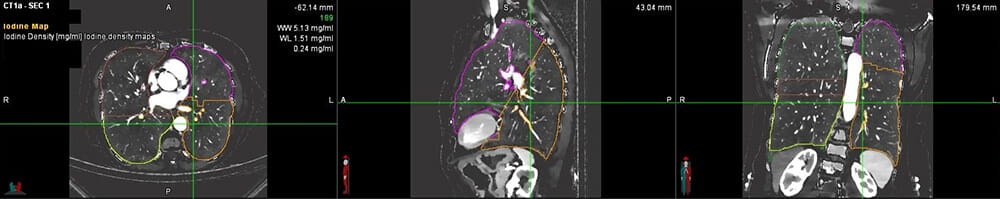

Dr. Avasarala received a CHEST Foundation grant to evaluate Dual Energy Computed Tomography (DECT) scans as an alternative to quantitative perfusion scans. He will be studying this with his co-investigator, Amit Gupta, MD, a DECT scanning expert in the Department of Radiology at University Hospitals Cleveland Medical Center. These DECT scans produce an iodine map that shows blood flow in the lungs.

Dual Energy Computed Tomography (DECT) scanDual Energy Computed Tomography (DECT) scan